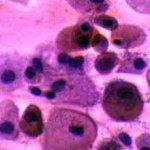

Πινακοθήκη κυτταρολογικών ευρημάτων ΙΙΙ

Οι πινακοθήκες κυτταρολογικών ευρημάτων, έχουν σαν στόχο να εμπλουτίσουν την κυτταρολογική εμπειρία σπουδαστών και ειδικευομένων, όπως ένας άτλαντας.

Παρουησιάζονται λοιπόν τυχαία ευρήματα, από το καθημερινό γυναικολογικό ιατρείο.